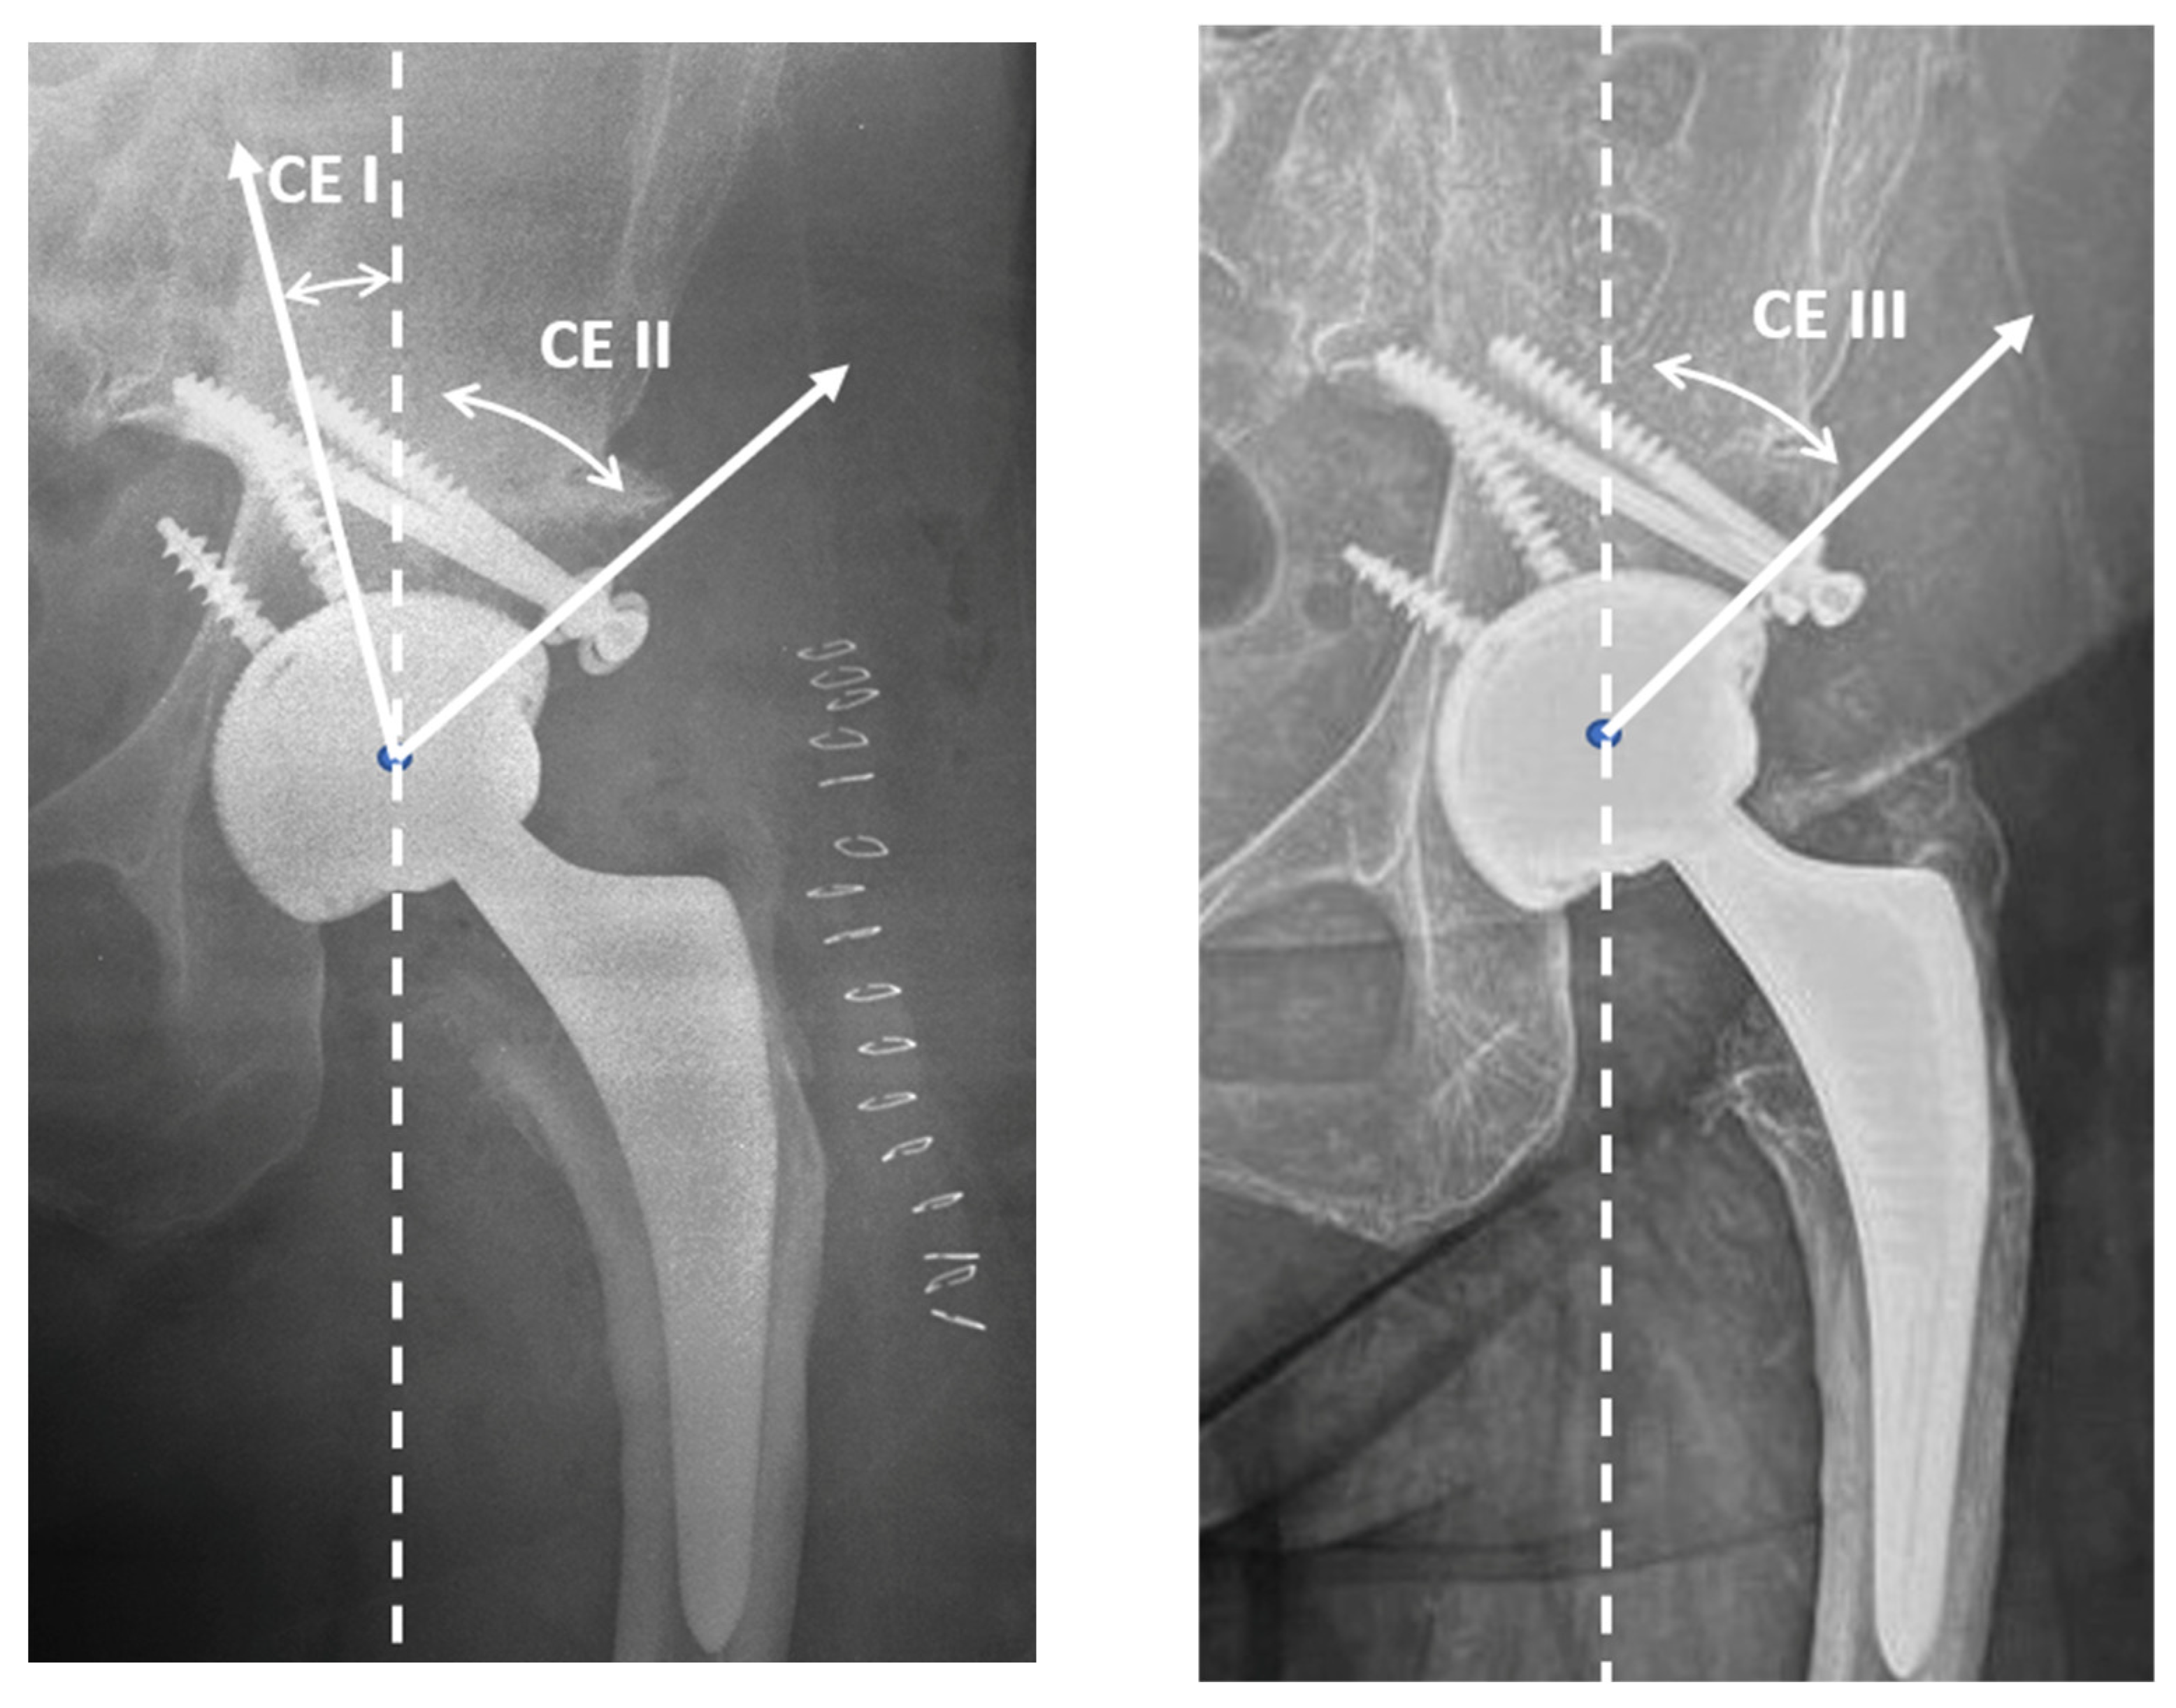

2.2. Radiological Assessment